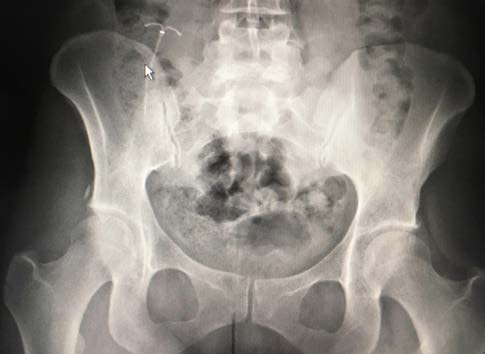

Em 2020, a doente foi referenciada pela médica de família a consulta de ginecologia para contraceção definitiva. Na consulta, foram solicitadas radiografias abdominal e pélvica, que revelaram um corpo estranho com a forma de “T” no quadrante superior direito do abdómen (Fig. 1), identificado como o SIU colocado dois anos antes.